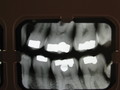

Shoes, Amalgams in 13,14,15,18,19,20; Amalgams in 2.3.4.30.31

Scar/mark: Scar on right hip. Scars on both legs. L-shaped scar on right ankle. Z-shaped scar on right knee. Triple in-line puncture wounds indicate traction device likely placed on left lower leg and right thigh.